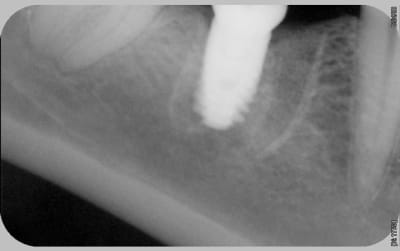

Il manque les radios du jour de la pose, j'ai l'impression que les implants ne sont pas assez enfouis . Pa exemple Anthogyr recommande de poser l'Axiom 0.5mm en sous crestal, que préconise Tekka ?

En ce qui concerne la radio de la 21 , on dirait qu'il a été mis dans un site d'extraction et qu'il n'est pas assez large.

voici les radios le jour de la pose

le krestal doit être en crestal et non en infra-osseux: il s'agit d'une connectique à plat et non d'un cône morse.

Je reviens là dessus car çà me semble être la clef

il me semble que sur le 1° cas présenté,la partie biseautée de l'implant est enfouie et que la cratérisation est nulle, idem pour l'implant mésial du dernier cas.

Sur son site Tekka préconise de mettre la partie supérieur de l'implant en juxtacrestal , donc le biseau est infraosseux...

J'avais rencontré le même pb sur un cas que j'avais présenté sur ce forum sur des IDcam et l'on m'avait fait remarqué à raison que l'enfouissement de l'implant distal était insuffisant, résultat a 6 mois cratérisation mésial et distal du dernier implant et à un an stabilisation .

Tu remarqueras que le biseau mésial de l'implant mésial qui a été correctement enfoui n'a pas bronché.